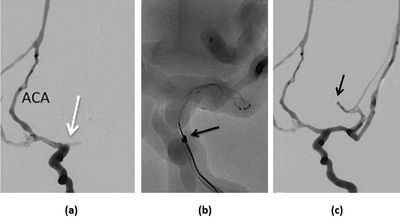

A DSA image shows a clot was placed & retrieved with a stent retriever from the left MCA.